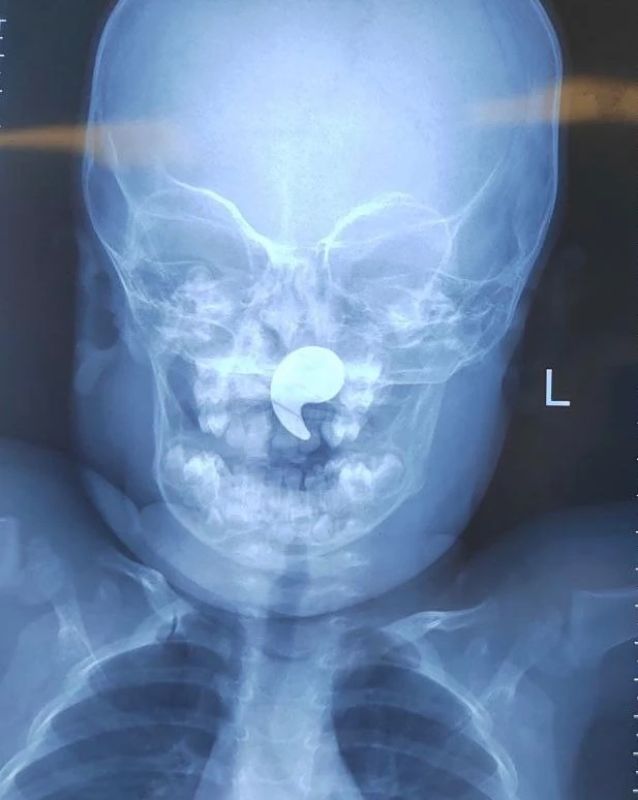

Детские врачи достали из носоглотки полуторагодовалой девочки магнит. Он попал туда во время игры. Необычным случаем из практики поделились в Минздраве Воронежской области.

Малышка играла магнитом в форме запятой. Мама девочки заметила, что она начала давиться, и попыталась извлечь опасную игрушку пальцем, но таким образом затолкала его в носоглотку.

Магнит в носоглотке мог привести к удушью и угрожал жизни ребёнка.

На рентгене выявили инородное тело, девочку сразу госпитализировали. Под общей анестезией магнит успешно достали под эндоскопическим контролем. Уже через сутки девочку выписали домой.